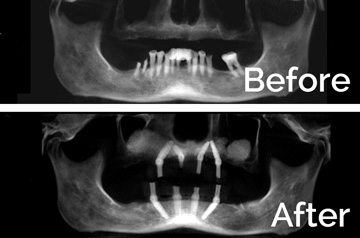

- Extractions with Alveoloplasty and Immediate Implants

- Temporary Denture Conversion into Temporary Bridge